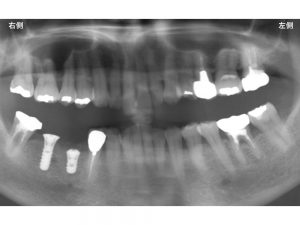

以下が手術直後です。

骨吸収の状態や神経との距離を考えての治療が必要です。